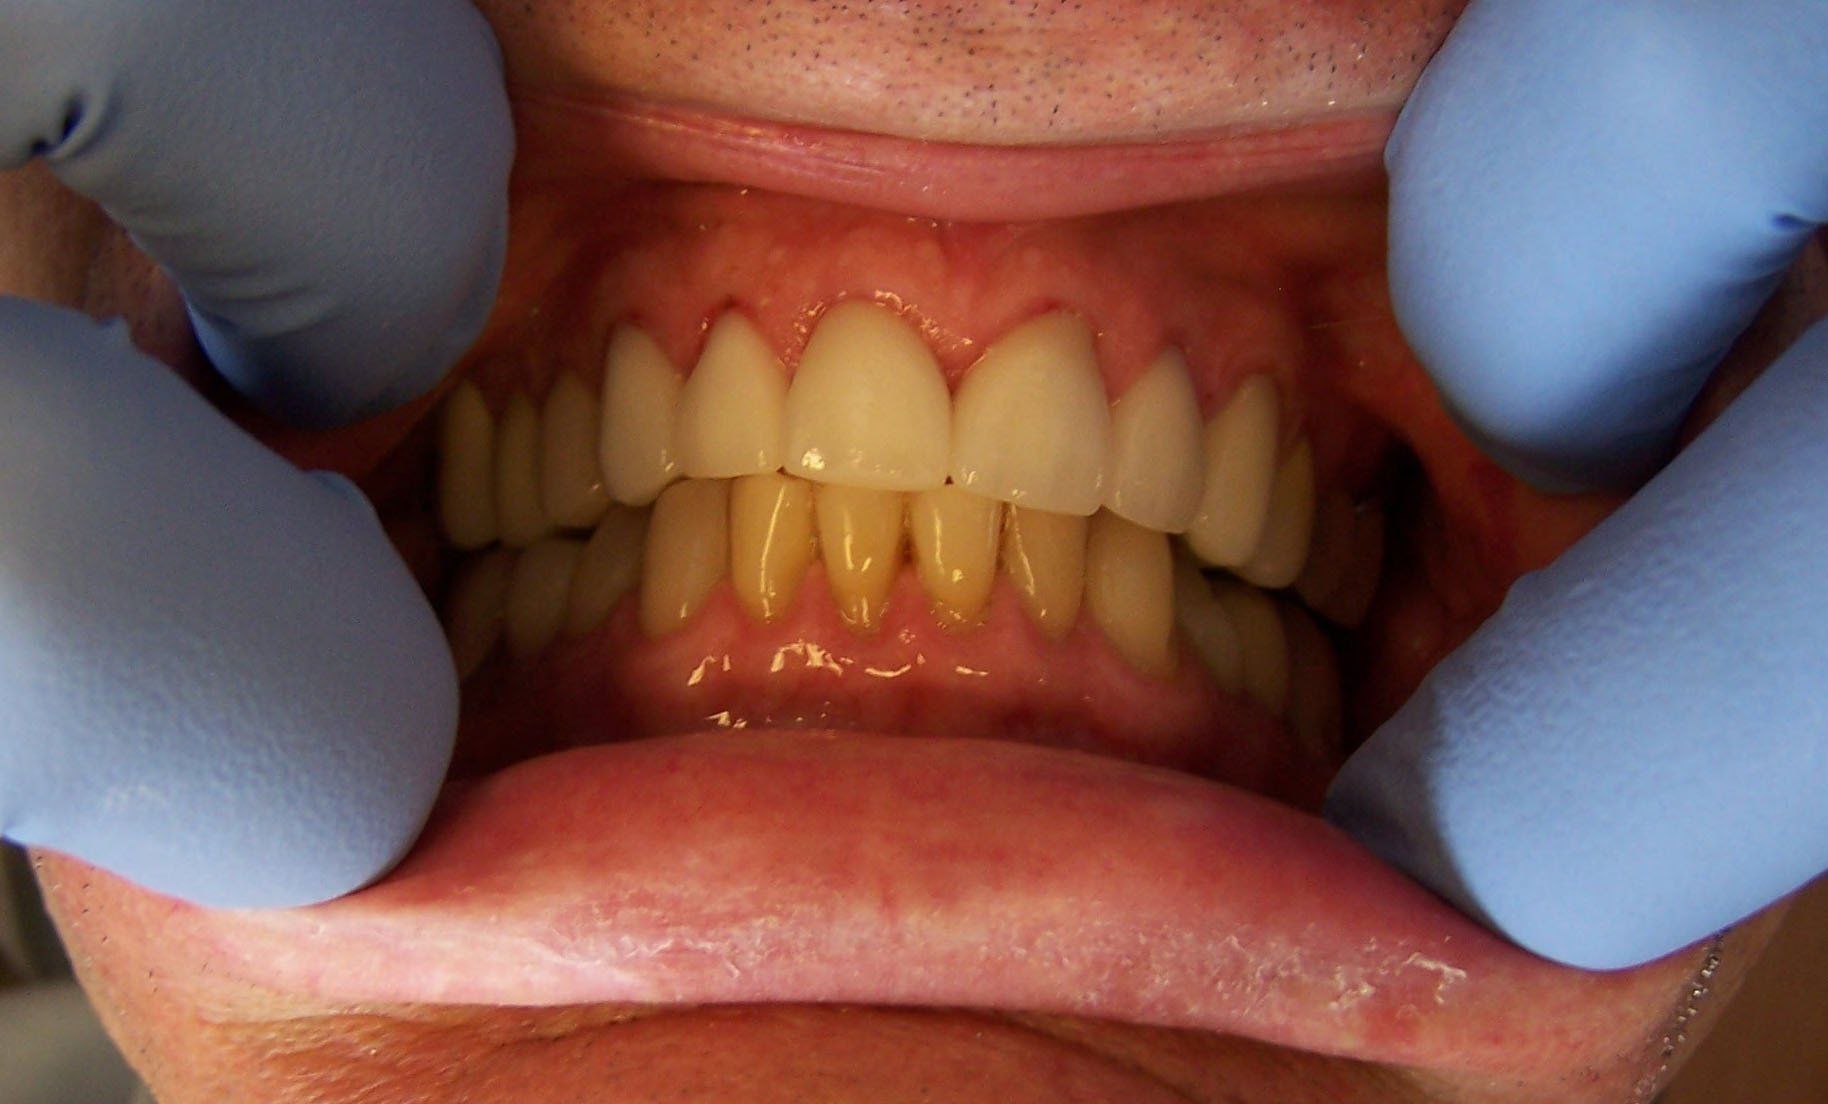

Holly Before

Button